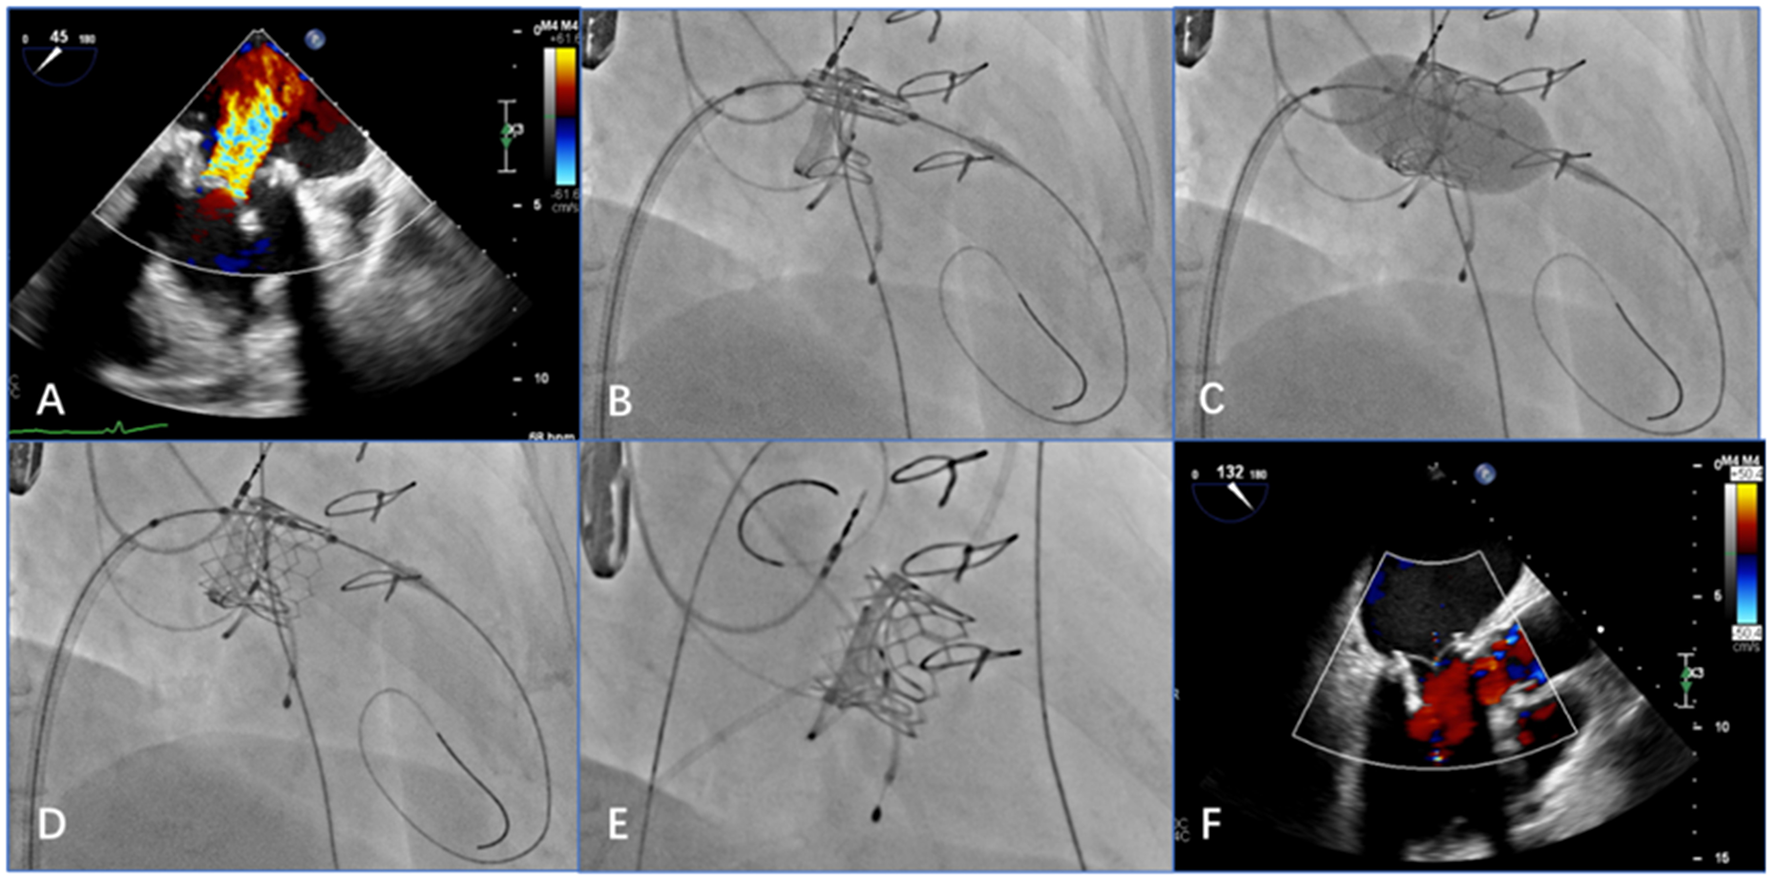

Systemic heparinization to achieve an activated coagulation time of >200s, a 6F pigtail catheter was placed in the left ventricle through the left femoral artery sheath; the right femoral vein was punctured and imported slowly with a 16F sheath inserted into the inferior vena cava. The atrial septum was punctured under the guidance of TEE and fluoroscopy, and the atrial septum was fully expanded with a 14-mm balloon. The pigtail catheter was delivered along the guide wire to the left atrium, then across the mitral valve to the left ventricle. Left ventriculography showed massive mitral regurgitation (Figure 4A). The Prizvalve catheter delivery system loaded with the 26-/29-mm valve was advanced along the guide wire into the left ventricle, crossing the atrial septum and the bioprosthetic annulus frame, and the delivery system can be smoothly passed by the guidance of the guide wire. After the release position was determined, rapid ventricular pacing reached 180 beats/min, and the balloon stent was fully expanded. After procedures, the antithrombotic regimen included aspirin and clopidogrel, and Patient 2 was treated by warfarin.

Figure 4

Transesophageal echocardiography (TEE) and digital subtraction angiography images show that the procedure achieved good results (e.g., data from patient 2). (A) Preprocedural TEE displays a large amount of colorful blood flow at the mitral valve. (B) The delivery system is positioned in relation to the mitral valve via the atrial septum. (C) After adjusting the position and the coaxiality, the balloon-expandable valve is inflated. (D) After expansion, the stent is fully unfolded. (E) When the guide wire is withdrawn, digital subtraction angiography shows that the position and shape of the mitral valve are ideal and that the stent fits closely to the valve. (F) Post-procedural TEE shows that the balloon-expandable valve is properly closed, with no paravalvular regurgitation.

Post-procedural TEE was used to examine the position and shape of the balloon-expanded valve and any regurgitation from the valve, which was consistent with the angiographic results (Figures 4B–F).